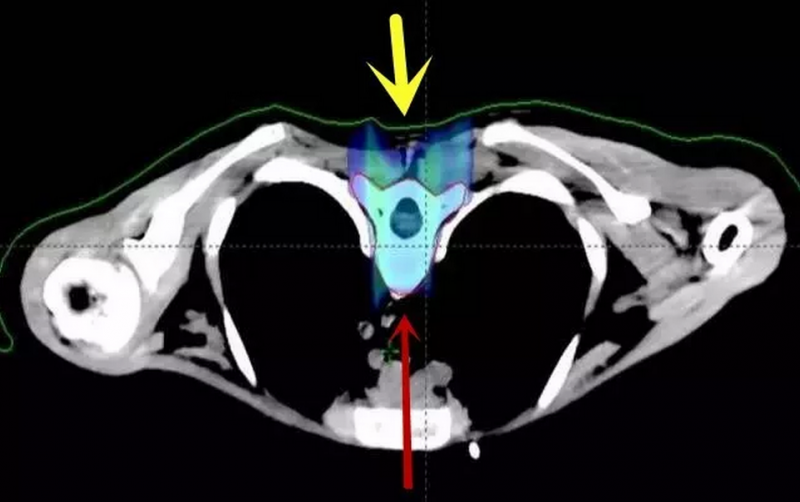

以下为全脑全脊髓质子剂量分布图:脊柱周围心肺胃肠等器官均未受照射